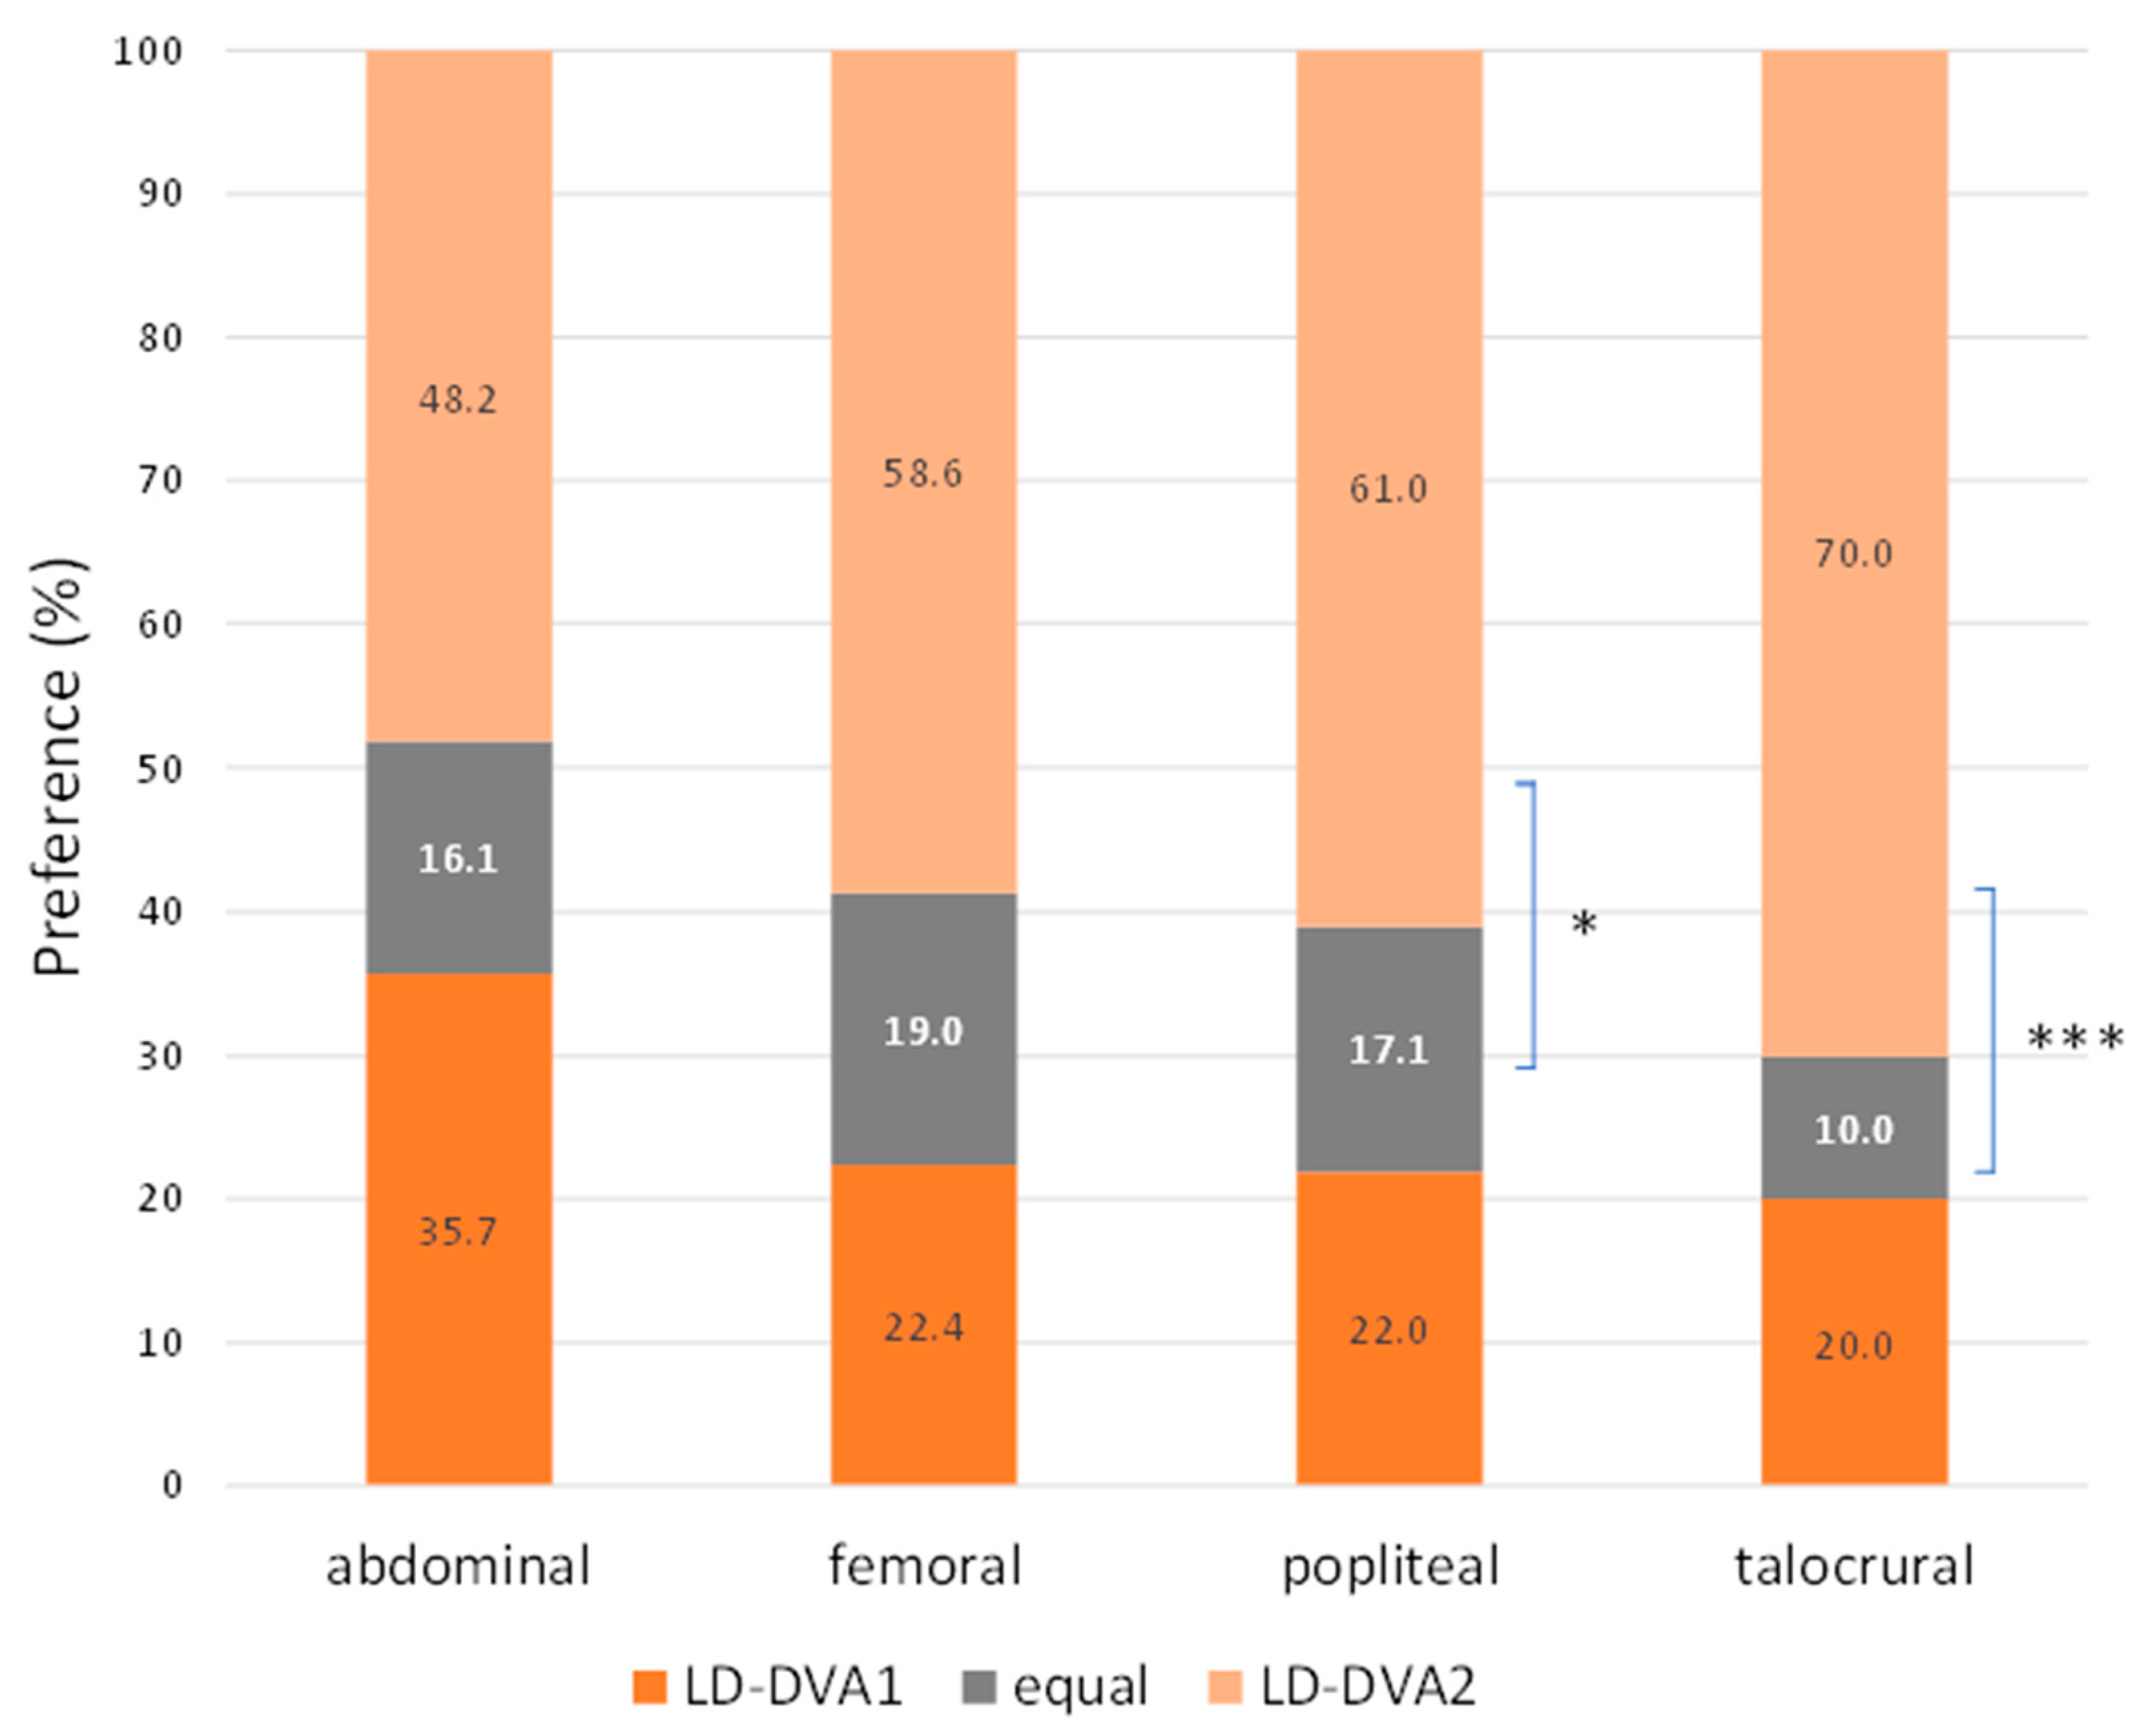

3.3. Visual Evaluation

| All | Median(SQR) | 3.83 (1.00) | 3.50 (1.17) | 3.83 (1.17) | 4.00 (0.83) | <0.001 |

| p (vs ND-DSA) | <0.001 | >0.999 | 0.028 | |||

| Mean ± SEM | 3.68 ± 0.05 | 3.35 ± 0.05 | 3.69 ± 0.05 | 3.89 ± 0.04 | ||

| Aortoiliac | Median(SQR) | 4.33 (0.66) | 4.00 (0.50) | 4.33 (0.54) | 4.33 (0.50) | 0.55 |

| p (vs ND-DSA) | 0.118 | >0.999 | >0.999 | |||

| Mean ± SEM | 4.20 ± 0.07 | 3.94 ± 0.06 | 4.21 ± 0206 | 4.24 ± 0.06 | ||

| Femoral | Median(SQR) | 4.16 (0.5) | 3.83 (0.66) | 4.17 (0.79) | 4.33 (0.50) | <0.001 |

| p (vs ND-DSA) | <0.001 | >0.9999 | 0.2024 | |||

| Mean ± SEM | 4.19 ± 0.05 | 3.79 ± 0.07 | 4.18 ± 0.06 | 4.35 ± 0.04 | ||

| Popliteal | Median(SQR) | 3.58 (1) | 3.17 (1.16) | 3.67 (0.87) | 4.00 (0.79) | <0.001 |

| p (vs ND-DSA) | 0.2711 | 0.1191 | <0.001 | |||

| Mean ± SEM | 3.41 ± 0.09 | 3.19 ± 0.09 | 3.67 ± 0.08 | 3.89 ± 0.08 | ||

| Talocrural | Median(SQR) | 3.41 (1.00) | 2.83 (1.00) | 3.17 (1.00) | 3.67 (1.00) | <0.001 |

| p (vs ND-DSA) | <0.001 | 0.8736 | ||||

| Mean ± SEM | 3.22 ± 0.08 | 2.7 ± 0.10 | 3.13 ± 0.08 | 3.44 ± 0.07 |